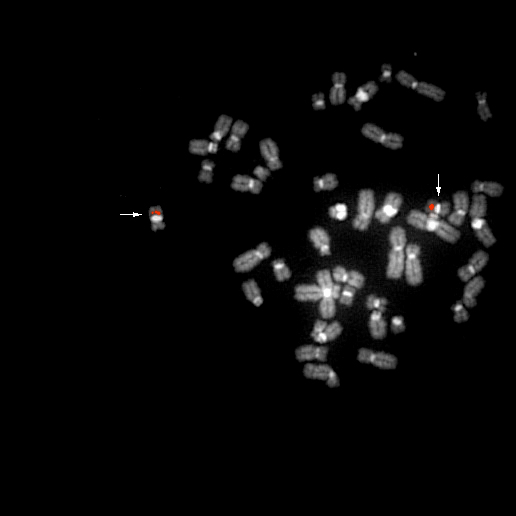

bA356O24